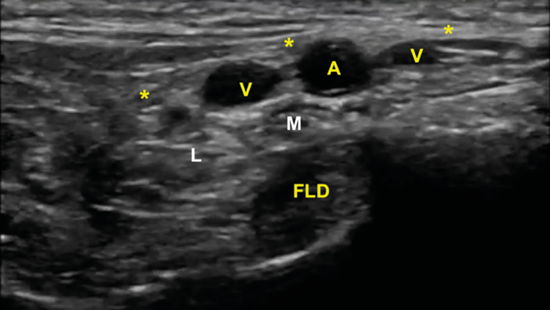

La imagen sonográfica se centrará en el espacio situado bajo la fascia profunda del músculo abductor del primer dedo, por donde discurrirán los haces neurovasculares plantar medial y plantar lateral, diferenciados y separados por el septo de Heimkes o interfascicular3. El nervio plantar medial se muestra con mayor sección que el nervio plantar lateral, y las venas laterales con mayor luz que las mediales (Figura 14).

Figura 14. El septo interfascicular (*) parte desde la fascia profunda del músculo abductor del primer dedo (ABD 1) hacia el tendón flexor largo del primer dedo (FLD) dividiendo la cámara superior de la cámara inferior, donde respectivamente se encuentran el haz neurovascular plantar medial (M: nervio plantar medial; A/V: arteria y venas plantar medial) y el haz neurovascular plantar lateral (L: nervio plantar lateral, A/V: arteria y venas plantar lateral). En profundidad, el músculo cuadrado plantar (QP) y la superficie del calcáneo (CAL).